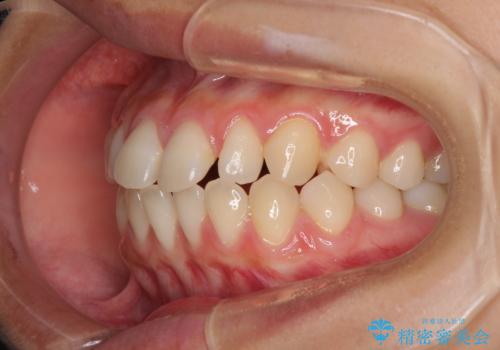

隙間だらけの歯列 インビザラインで改善

- 前歯の上下スペースと前歯の隙間を気にして来院された患者様です。

飲み込みや話をするときに舌を突出させる癖が強くあり、それが原因でスペースが空いていました。

舌癖を改善するためのトレーニングを行いながら、インビザラインにより上下の前歯の隙間を閉じていくこととしました。